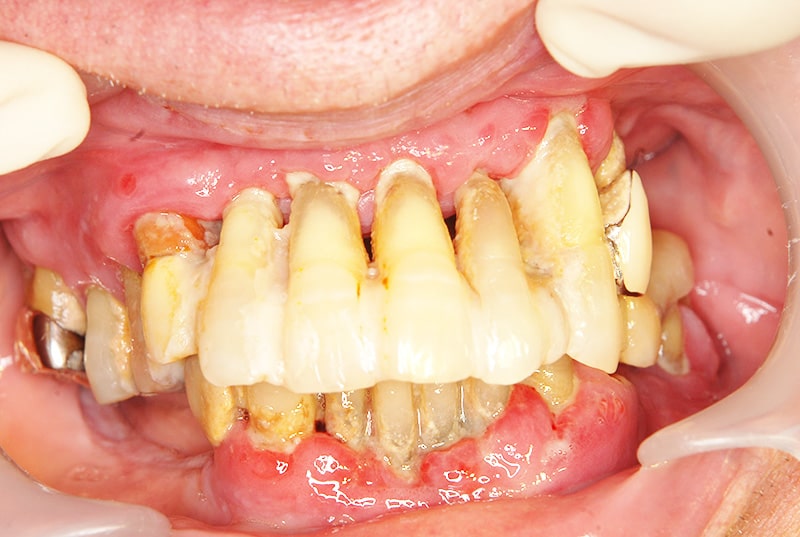

症例4【60代女性】臼歯部が崩壊して奥歯で物が噛めない

治療前

治療後

※説明

主訴 下顎臼歯部のインプラント周囲炎を併発している。又、上顎臼歯部においては歯周病が進行しており、咀嚼ができない状態である。インプラント周囲炎に関しては、インプラント体を撤去し力学的に安定した位置に1本のみ埋入。

上顎は、臼歯部に採血で得られるCGFメンブレンとAFG(人工骨β―TCPとAFGを混ぜたブロック)を併用したソケットリフト(骨造成)を行い、

インプラントを4本埋入。オペから仮歯を経て最終補綴物ジルコニア装着まで約5カ月を要した。

リスクとしては、ソケットリフト(骨造成)による一過性の副鼻腔炎が起きる可能性がある。まれに洞底膜が破れる可能性がある。

ただし、膜は約3週で再生するので、膜の回復を待ち、再オペを行う。

費用 276万(オペ・ソケットリフト・人工骨・採血による濃縮血小板生成・仮歯・最終補綴物まで含む)